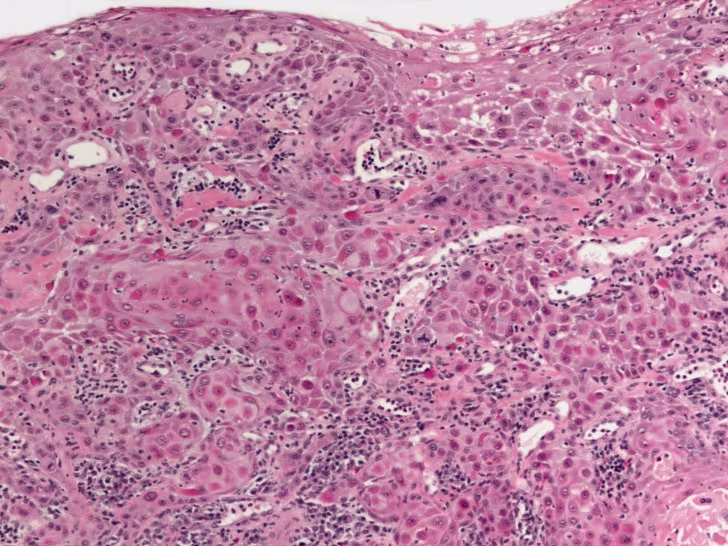

Histopathologic Findings The histologic sections of the incisional biopsy show infiltrating cords and islands of atypical squamous epithelium arising from dysplastic surface mucosa. There is a supporting fibrovascular connective tissue stroma with lymphocytic interface chronic inflammatory infiltrate. The epithelial cells displays pleomorphic round to oval nuclei with finely dispersed to vesicular chromatin, prominent nucleoli, increased nuclear to cytoplasmic ratio and pink focally dyskeratotic cytoplasm. There are numerous abnormal mitotic figures and focal single apoptotic cells.

Figure 3. Low power histologic image showing invasive cords and islands of squamous epithelium extending into chronically a inflamed fibrovascular connective tissue stroma. The surface mucosa is dysplastic and parakeratotic.